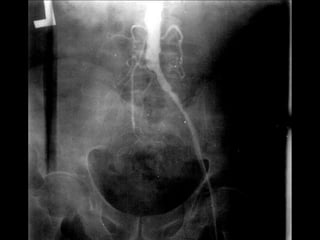

 -Angiography

- Arteriography

Arteriography

1- Laboratory investigations: 2-Imaging:  - Doppler flow study. ABI Segmental pressure  - Duplex scanning  -Angiography

1- Laboratory investigations: 2-Imaging: - Doppler flow study. • ABI • Segmental pressure - Duplex scanning - Arteriography Arteriography